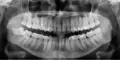

Вчера была у стоматолога. Предположение ― пульпит 8-ки, нужно удаление. Это первый коренной зуб, который предстоит удалить. Большой страх перед этой процедурой. Читала много, боюсь, чтобы не повредили лишнего. Корни 8-ки загнуты. Боюсь, чтоб они не лежали в нервном канале, и при удалении не было проблем.

Прикрепленые фото